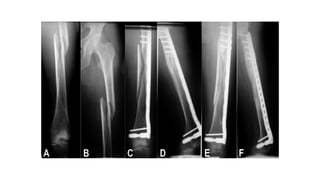

This document discusses femoral fractures, categorized by their location and severity, with classifications such as Garden classification. It outlines the types of fractures, including valgus impacted, non-displaced, partially displaced, and fully displaced, along with their surgical treatment options. Additionally, it briefly describes distal femur fractures, which occur just above the knee joint.